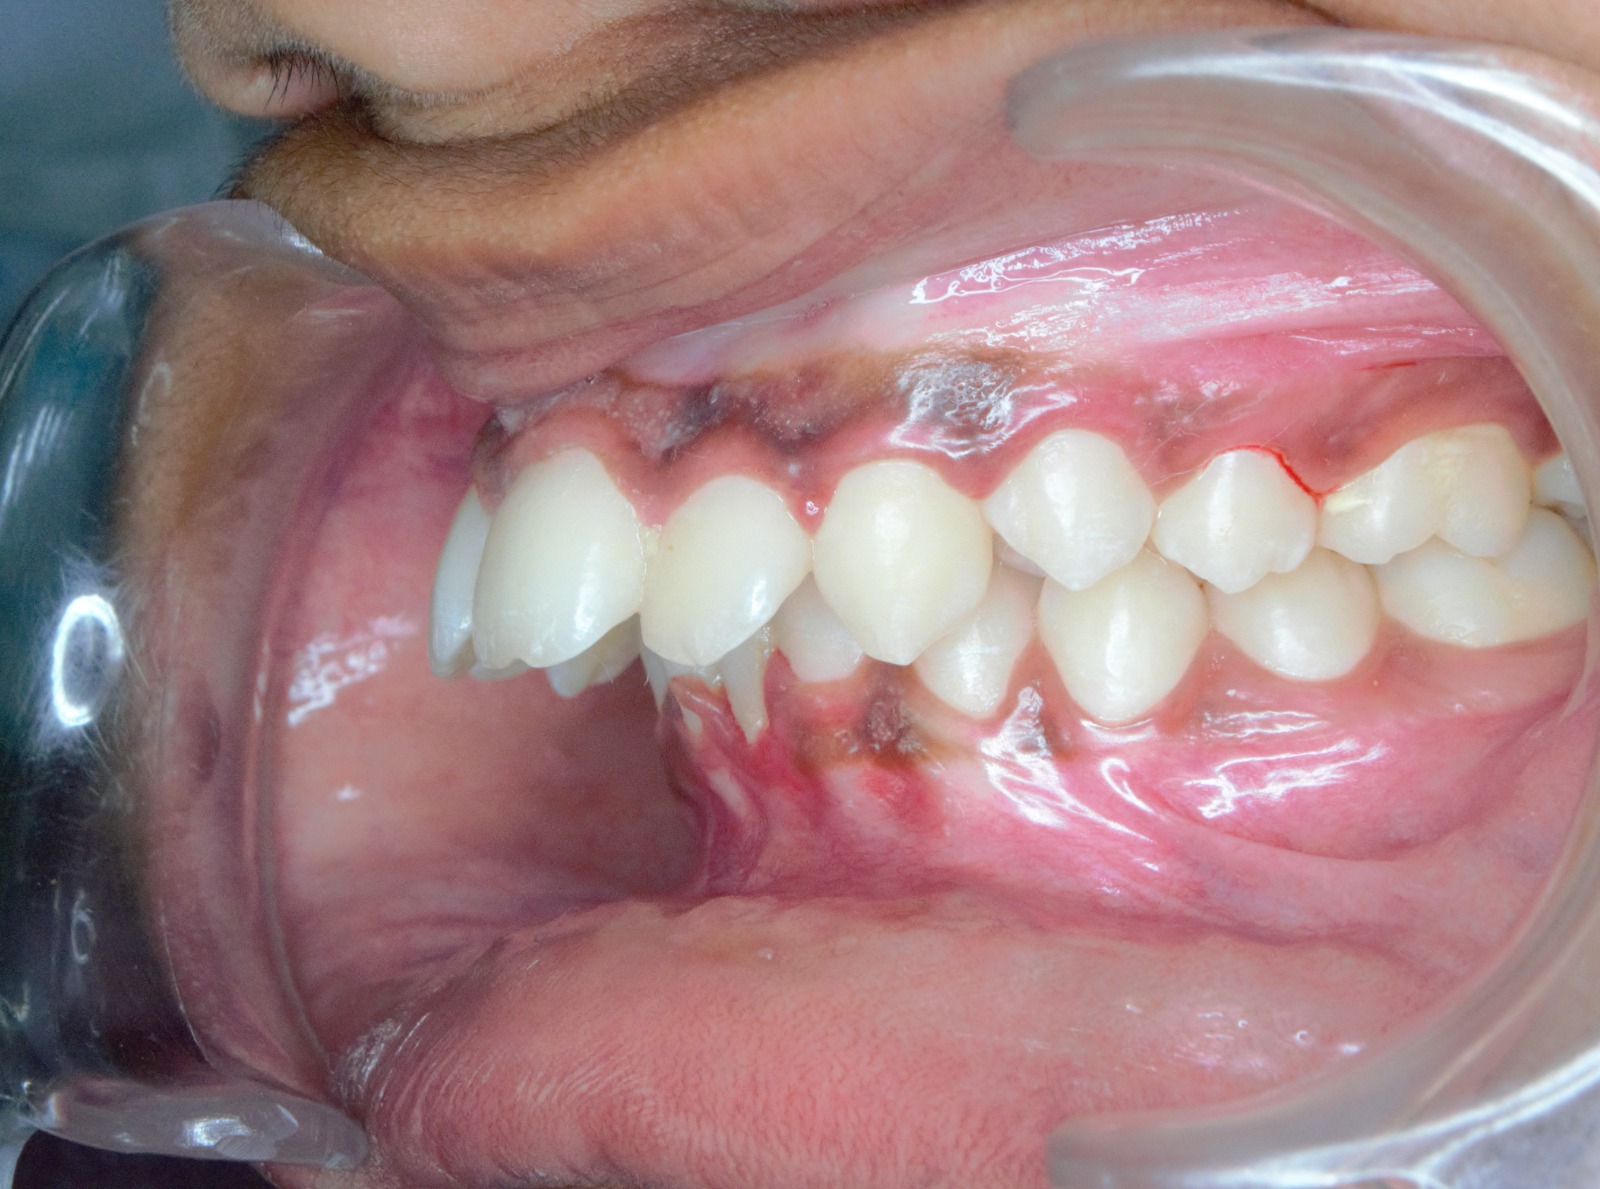

After/Before

See stunning smile transformation before and after

Before After